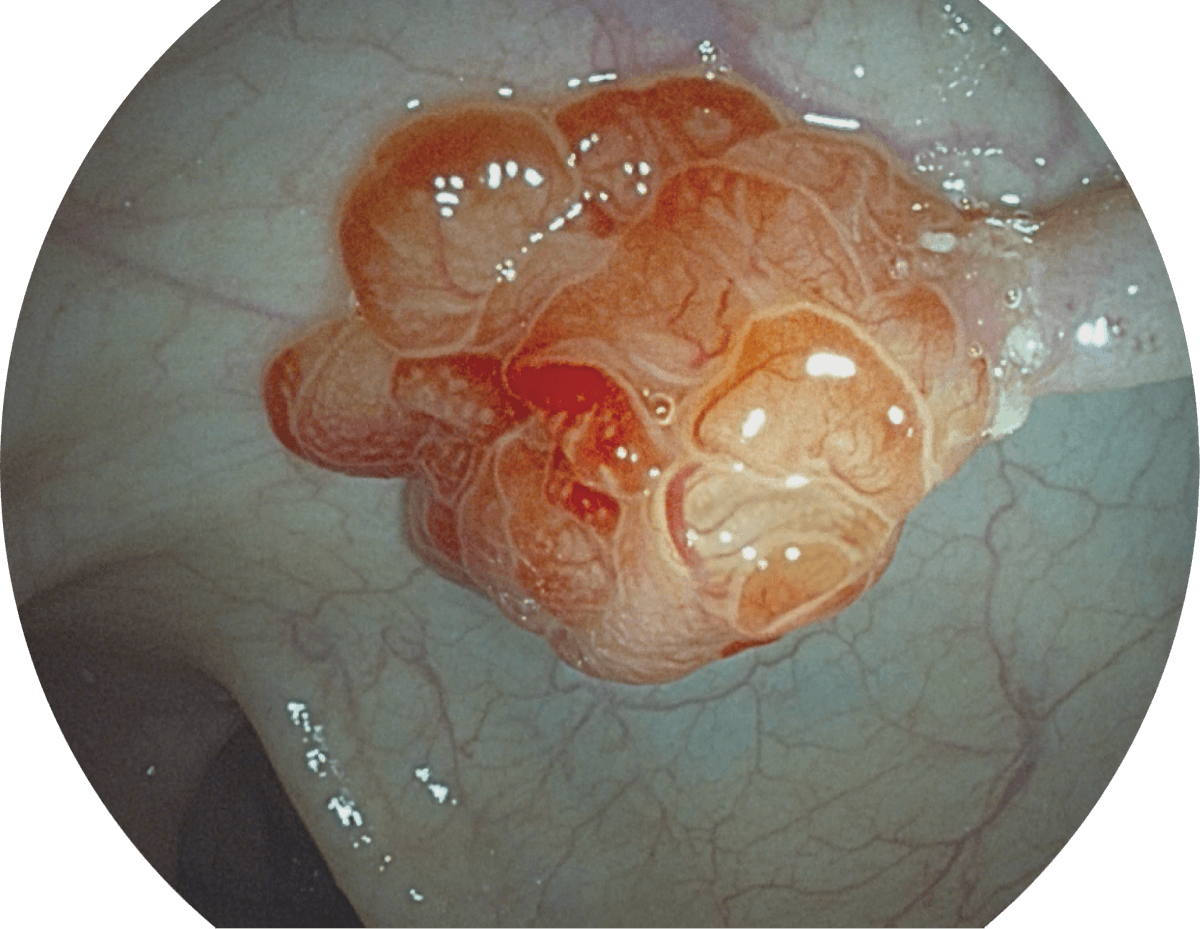

具有聚谱成像技术(SFI)及光电复合染色成像技术(VIST),可完美呈现粘膜细节及病变特征。

SFI

VIST